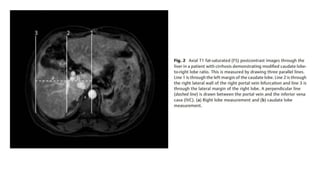

• The modified caudate-to-right lobe ratio with the right portal vein as

the lateral border and an abnormal value >0.9 had higher accuracy.

• Cross-sectional imagingis better to depict morphological abnormalities. • The modified caudate-to-right lobe ratio with the right portal vein as the lateral border and an abnormal value >0.9 had higher accuracy. • The right posterior hepatic notch sign indicates a sharp indentation along the right posteromedial surface of the liver between the hypertrophied caudate and the atrophic right posterior segment. • Widened porta hepatis anterior to the main portal vein at the hilum is also associated with cirrhosis

• #13 Axial venous phase images of contrast enhanced CT (A) right posterior hepatic notch sign and (B) volume redistribution with widened porta hepatis.